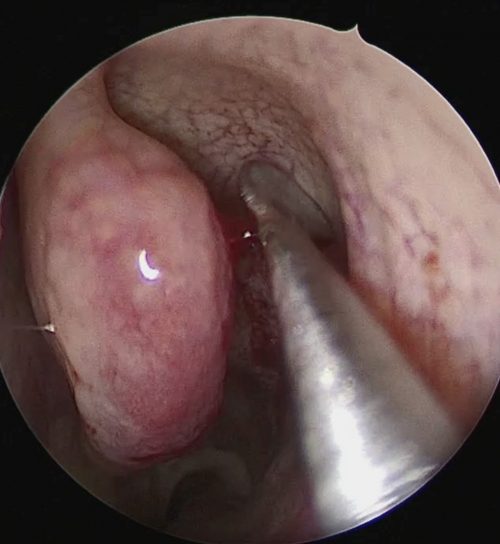

Atualmente meu método de escolha para a cirurgia da adenoide é por videoendoscopia, por dentro do nariz e da boca com visualização direta do tecido removido e pontos sangrantes. Alguns materiais especiais são utilizados na remoção da adenoide para garantirmos um menor sangramento e sua remoção completa, por exemplo: Shaver angulado (microdebridador), ponteira de Radiofrênquia.